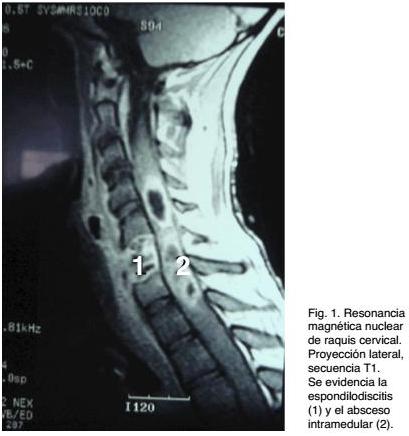

Se estudia primero con RX y Tomografía Computada de raquis cervical, que confirmaron lesión compatible con espondilodiscitis C5-C6. Posteriormente se completó con una Resonancia Magnética (RM) de todo el raquis, que evidencia a nivel cervical: lesión compatible con espondilodiscitis C5-C6 sin listesis y colección prevertebral compatible con absceso. A nivel medular se evidencia un proceso centrado en la zona de la espondilodiscitis, con ensanchamiento medular, con áreas hiperintensas y otras hipointensas, compatibles con un extenso absceso acompañado de edema (Figura 1).

Si bien se reportan casos en los que no había foco infeccioso demostrable ni de vecindad ni a distancia, en el caso analizado en esta presentación había un foco infeccioso de vecindad (espondilodiscitis). En el mismo, la imagenología simple (RX de columna cervical) y la Tomografía Computada de raquis fueron positivas en demostrar una lesión discovertebral, con las características de una espondilodiscitis C5-C6, con alteraciones vertebrales, secundarias a osteomielitis. Estas lesiones explican el cuadro doloroso de semanas de evolución, tipificado como dolor raquídeo y el síndrome toxi-infeccioso de los días previos al ingreso. Por el déficit neurológico, que evolucionó rápidamente, se solicitó una RM de raquis, que evidenció una extensa lesión medular, con aspecto de un absceso multilobulado asociado a edema y ensanchamiento medular cervical. Se destaca que no había compromiso epidural ni subdural. El proceso patológico medular estaba centrado en la topografía de la lesión discovertebral, pero no había evidencia imagenológica de continuidad. La terapéutica quirúrgica requirió dos intervenciones, una de emergencia para evacuar el absceso, dado lo severo del déficit neurológico y una segunda a las 48 hs y ya estabilizado el paciente, donde se realizó la corporectomía y posterior instrumentación raquídea. A pesar del tratamiento quirúrgico y del tratamiento empírico con antibióticos instituido desde el ingreso, la evolución no fue buena. A las 72 hs. de la segunda cirugía fallece, dado que había evolucionado a un cuadro infeccioso generalizado con repercusión multisistémica (shock séptico).